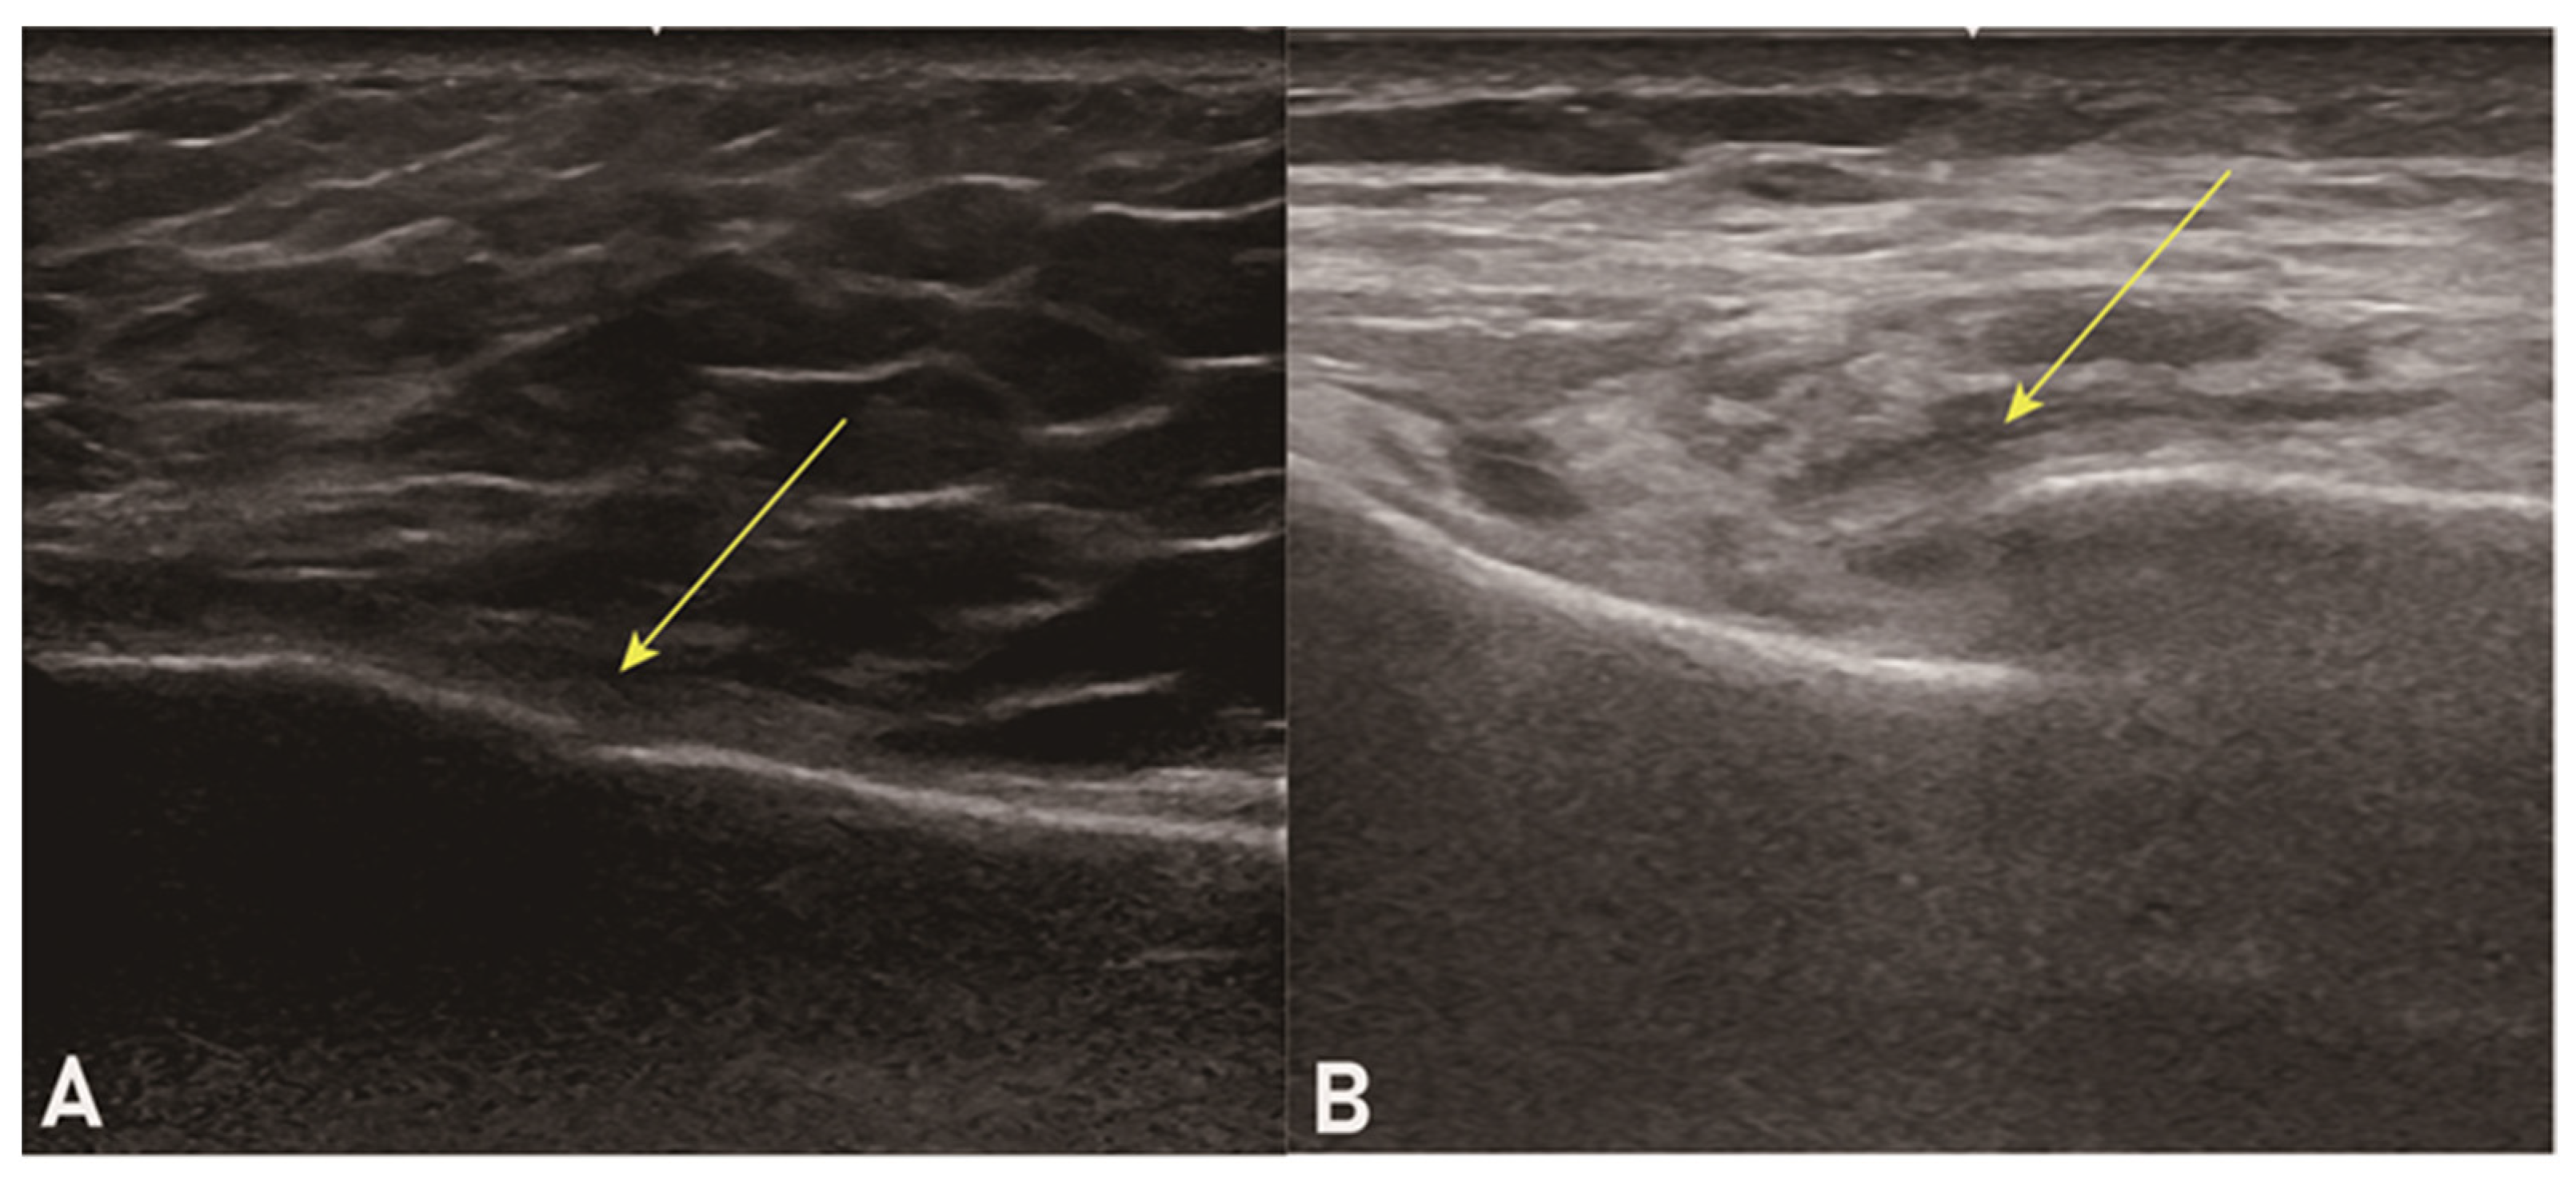

Sternal ultrasound was performed by two trauma surgeons skilled in sonography, whose experience with ultrasound examination amounted to 6 and 7 years, respectively. The indication for sternal ultrasound was determined when the patient complained of anterior chest wall pain at the time of the visit, with positive tenderness. It was implemented following EFAST. The sternum was evaluated longitudinally using a linear probe. The diagnosis of a sternal fracture was obtained when a loss of continuity in the sternal cortex was observed (Figure 2) and the location of the maximum point of tenderness on the probe coincided with the location of the loss of continuity in the sternal cortex.

Figure 2. Two example images of sternal ultrasound showing positive findings with loss of continuity in the sternal cortex (arrows) ((A): minimal displacement, (B): moderate displacement).